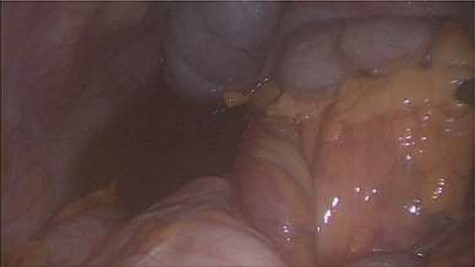

Emergency diagnostic laparoscopy was performed and findings were: 180 degree volvulus of terminal ileum, cecum and ascending colon overlapped each other and overriding the right loop of the liver, the lateral attachment of the right colon was long dilated and floppy (Figs 5 and 6). The dudeno-jejenal flexure was malrotated and lying in left upper quadrant just below to splenic flexure. Three congenital bands were found tilted around the terminal ileum, cecum and base of the appendix. Turbid free fluids with no evidence of infection also noted in the right upper quadrant and right para-colic gutter (Fig. 7). Otherwise, bowels were found healthy and viable. A healthy retrocecal and subserosal appendix was also noted intraoperatively. We converted to open Laparotomy and proceeded with right hemicolectomy due to complex intraoperative findings. The postoperative period was uneventful, and patient was discharged at home on postoperative Day 7.

Showing floppy dilated cecum ileum and ascending colon twisted around the liver and mesentery.